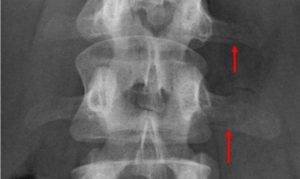

Перелом поперечного отростка позвонка на рентгене

Основные причины перелома поперечного отростка позвонка:

Рентгенография применяется редко, так как может дать неточные результаты, особенно если во время диагностики у пациента имеется избыток кишечных газов (они дают ложные «тени» на снимке).